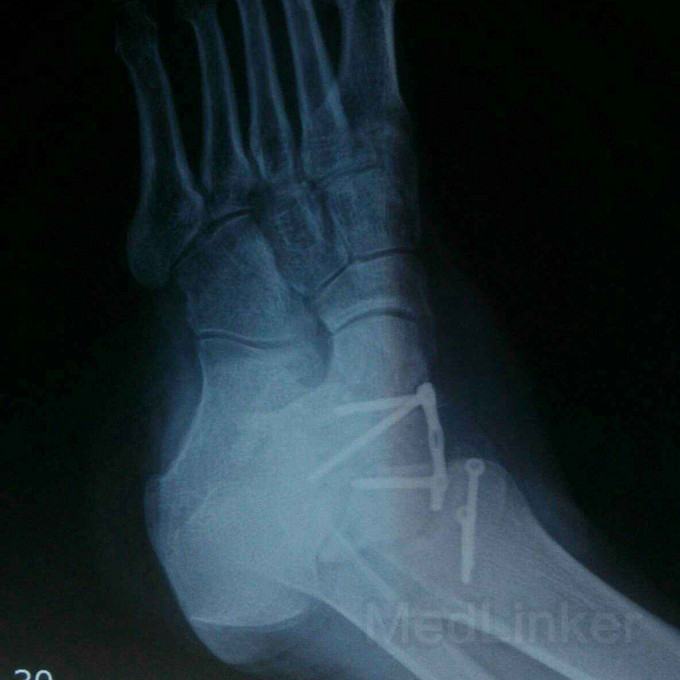

距骨术后一年余局部肿胀?

距骨骨折

外伤致右足距骨骨折,行钢板内固定术后半年余,现右足肿胀,影响行走,踝关节无法活动,该用什么办法好